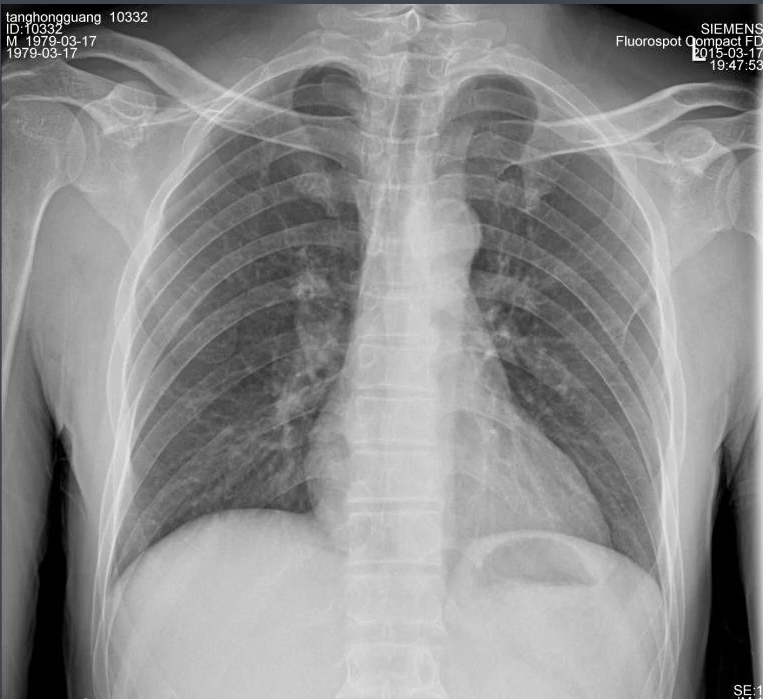

X射線,是一種頻率極高,波長極短、能量很大的電磁波。具有穿透性,但人體組織間有密度和厚度的差異,當(dāng)X射線透過人體不同組織時(shí),被吸收的程度不同,經(jīng)過顯像處理后即可得到不同的影像。下面那我們來聊一聊關(guān)于X射線的三大特性分別是哪些。

X射線因其波長短,能量大,照在物質(zhì)上時(shí),僅一部分被物質(zhì)所吸收,大部分經(jīng)由原子間隙而透過,表現(xiàn)出很強(qiáng)的穿透能力。X射線穿透物質(zhì)的能力與X射線光子的能量有關(guān),X射線的波長越短,光子的能量越大,穿透力越強(qiáng)。X射線的穿透力也與物質(zhì)密度有關(guān),利用差別吸收這種性質(zhì)可以把密度不同的物質(zhì)區(qū)分開來 。

X射線同可見光一樣能使膠片感光。膠片感光的強(qiáng)弱與X射線量成正比,當(dāng)X射線通過人體時(shí),因人體各組織的密度不同,對(duì)X射線量的吸收不同,膠片上所獲得的感光度不同,從而獲得X射線的影像 。